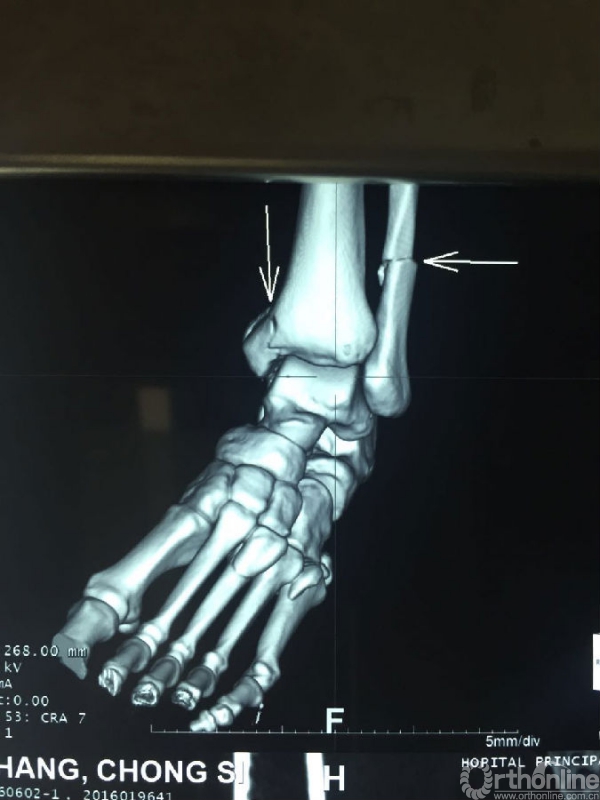

战士司崇昶,因31日的爆炸恐怖袭击导致全身多处创伤,左耳廓、颌面部炸伤,左踝开放性粉碎性骨折,面部及左下肢神经损伤。在初步清创缝合包扎后转入ICU病房。杨润功教授到达ICU病房后,仔细询问了病情,查看伤口情况,重新给予下肢石膏固定,并详细叮嘱康复锻炼要点。目前司崇昶生命体征平稳,饮食状态已有所好转。

司崇昶踝关节CT